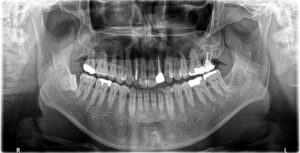

③含歯性嚢胞摘出約6か月後

①の病変は口蓋側まで及んでいたため一部が瘢痕治癒していると考えられますが、

特に問題なく経過しております。

②、③は治癒しております。